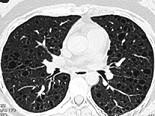

问题 女,34岁,气喘伴呼吸困难1个月并加重,CT如图,最可能的诊断为 ( )

选项 A.多发性肺囊肿 B.肺淋巴管肌瘤病 C.小叶性肺气肿 D.金葡菌感染并肺气囊形成 E.支气管扩张

答案 B